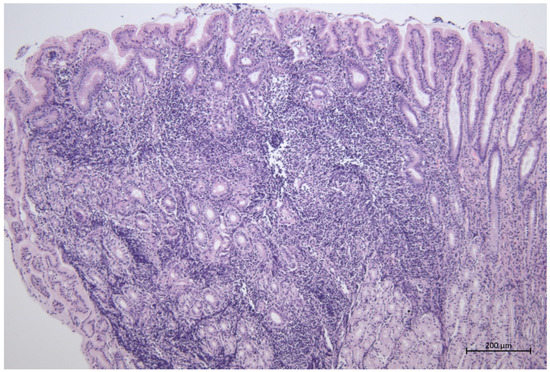

3.1. Duodenal Mucosal Samples

3.1.1. Superficial Epithelium

3.1.2. Lamina Propria

3.1.3. Submucosa

3.2. Rectal Mucosal Samples

3.2.1. Superficial Epithelium

3.2.2. Lamina Propria

3.2.3. Submucosa